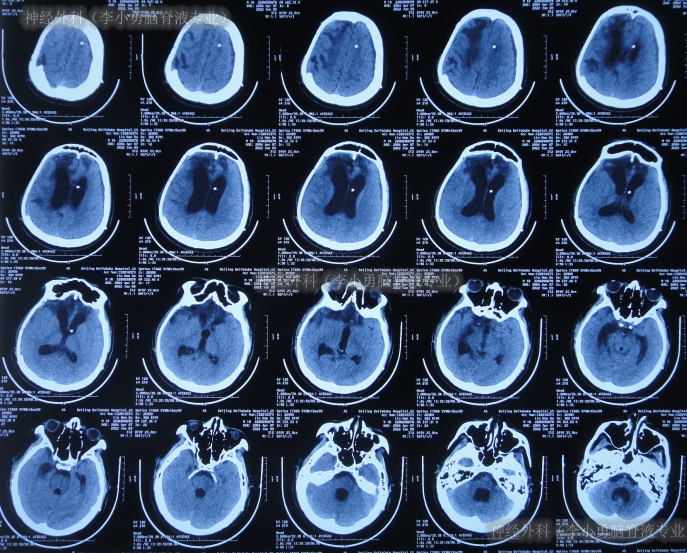

继续治疗1月期间出现数次呕吐,行胃肠镜检查未见异常(片子丢失),给予胃管及肠管置管,期间5次查头颅CT(图-5)均示脑室逐渐出现扩张,并加重。

图-5:5次查头颅CT

去骨瓣减压术后36天即2022年3月9日,复查头颅CT(图-6)示脑室扩张更严重了,脑膨出。

图-6:2022年3月9日头颅CT

去骨瓣减压术后43天即2022年3月16日,查头颅CT示仍严重脑积水(图-7)。

图-7:2022年3月16日头颅CT